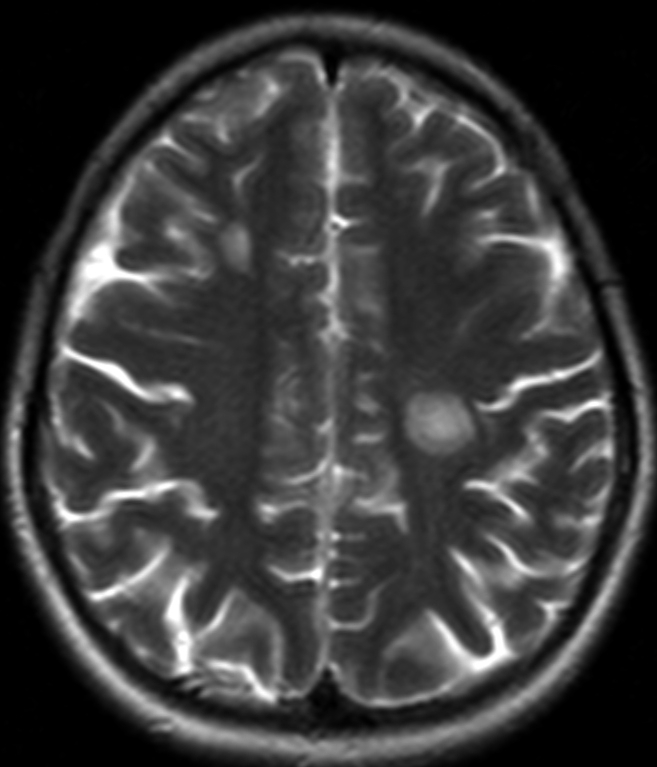

Демиелинизирующие заболевания мозга: МРТ изображения